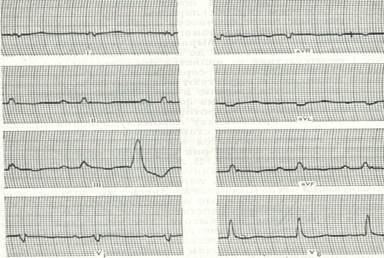

Хлопчик 10 років. Скарги на підвищення температури тіла, в'ялість, дворазову блювоту, підвищену пітливість, появу набряків на нижніх кінцівках. Два тижні тому прооперований з приводу вродженої вади серця, в задовільному стані виписаний додому. Об¢єктивно: відставання в фізичному розвитку, блідість із ціанотичним відтінком шкірних покривів, пітливість, деформація пальців рук та ніг у вигляді "барабанних паличок" та нігтів у вигляді "годинникових скелець". Температура тіла 37,8°С, пульс 140 на хв, дихання 24 на хв, артеріальний тиск 80/40 мм рт.ст. На грудній клітці свіжий рубець після операції на серці. Межі серця різко розширені, права на 1,5 см назовні від парастернальпої лінії, ліва доходить до середньо-підпахвинної лінії. При натискуванні фонендоскопом вислуховується ніжний шум тертя перикарду на фоні послабленої гучності серцевих тонів. Над легенями провідні хрипи, більше в паравертебральній ділянці. Печінка на 4-5 см виступає з під реберної дуги. На нижніх кінцівках відмічається пастозність. ЕКГ,  ЕхоКГ та рентгенограма додається.

ЕхоКГ та рентгенограма додається.

1. Попередній діагноз. Назвати основні симптоми захворювання.

2. Лікувальна тактика.

3. Надати невідкладну допомогу.